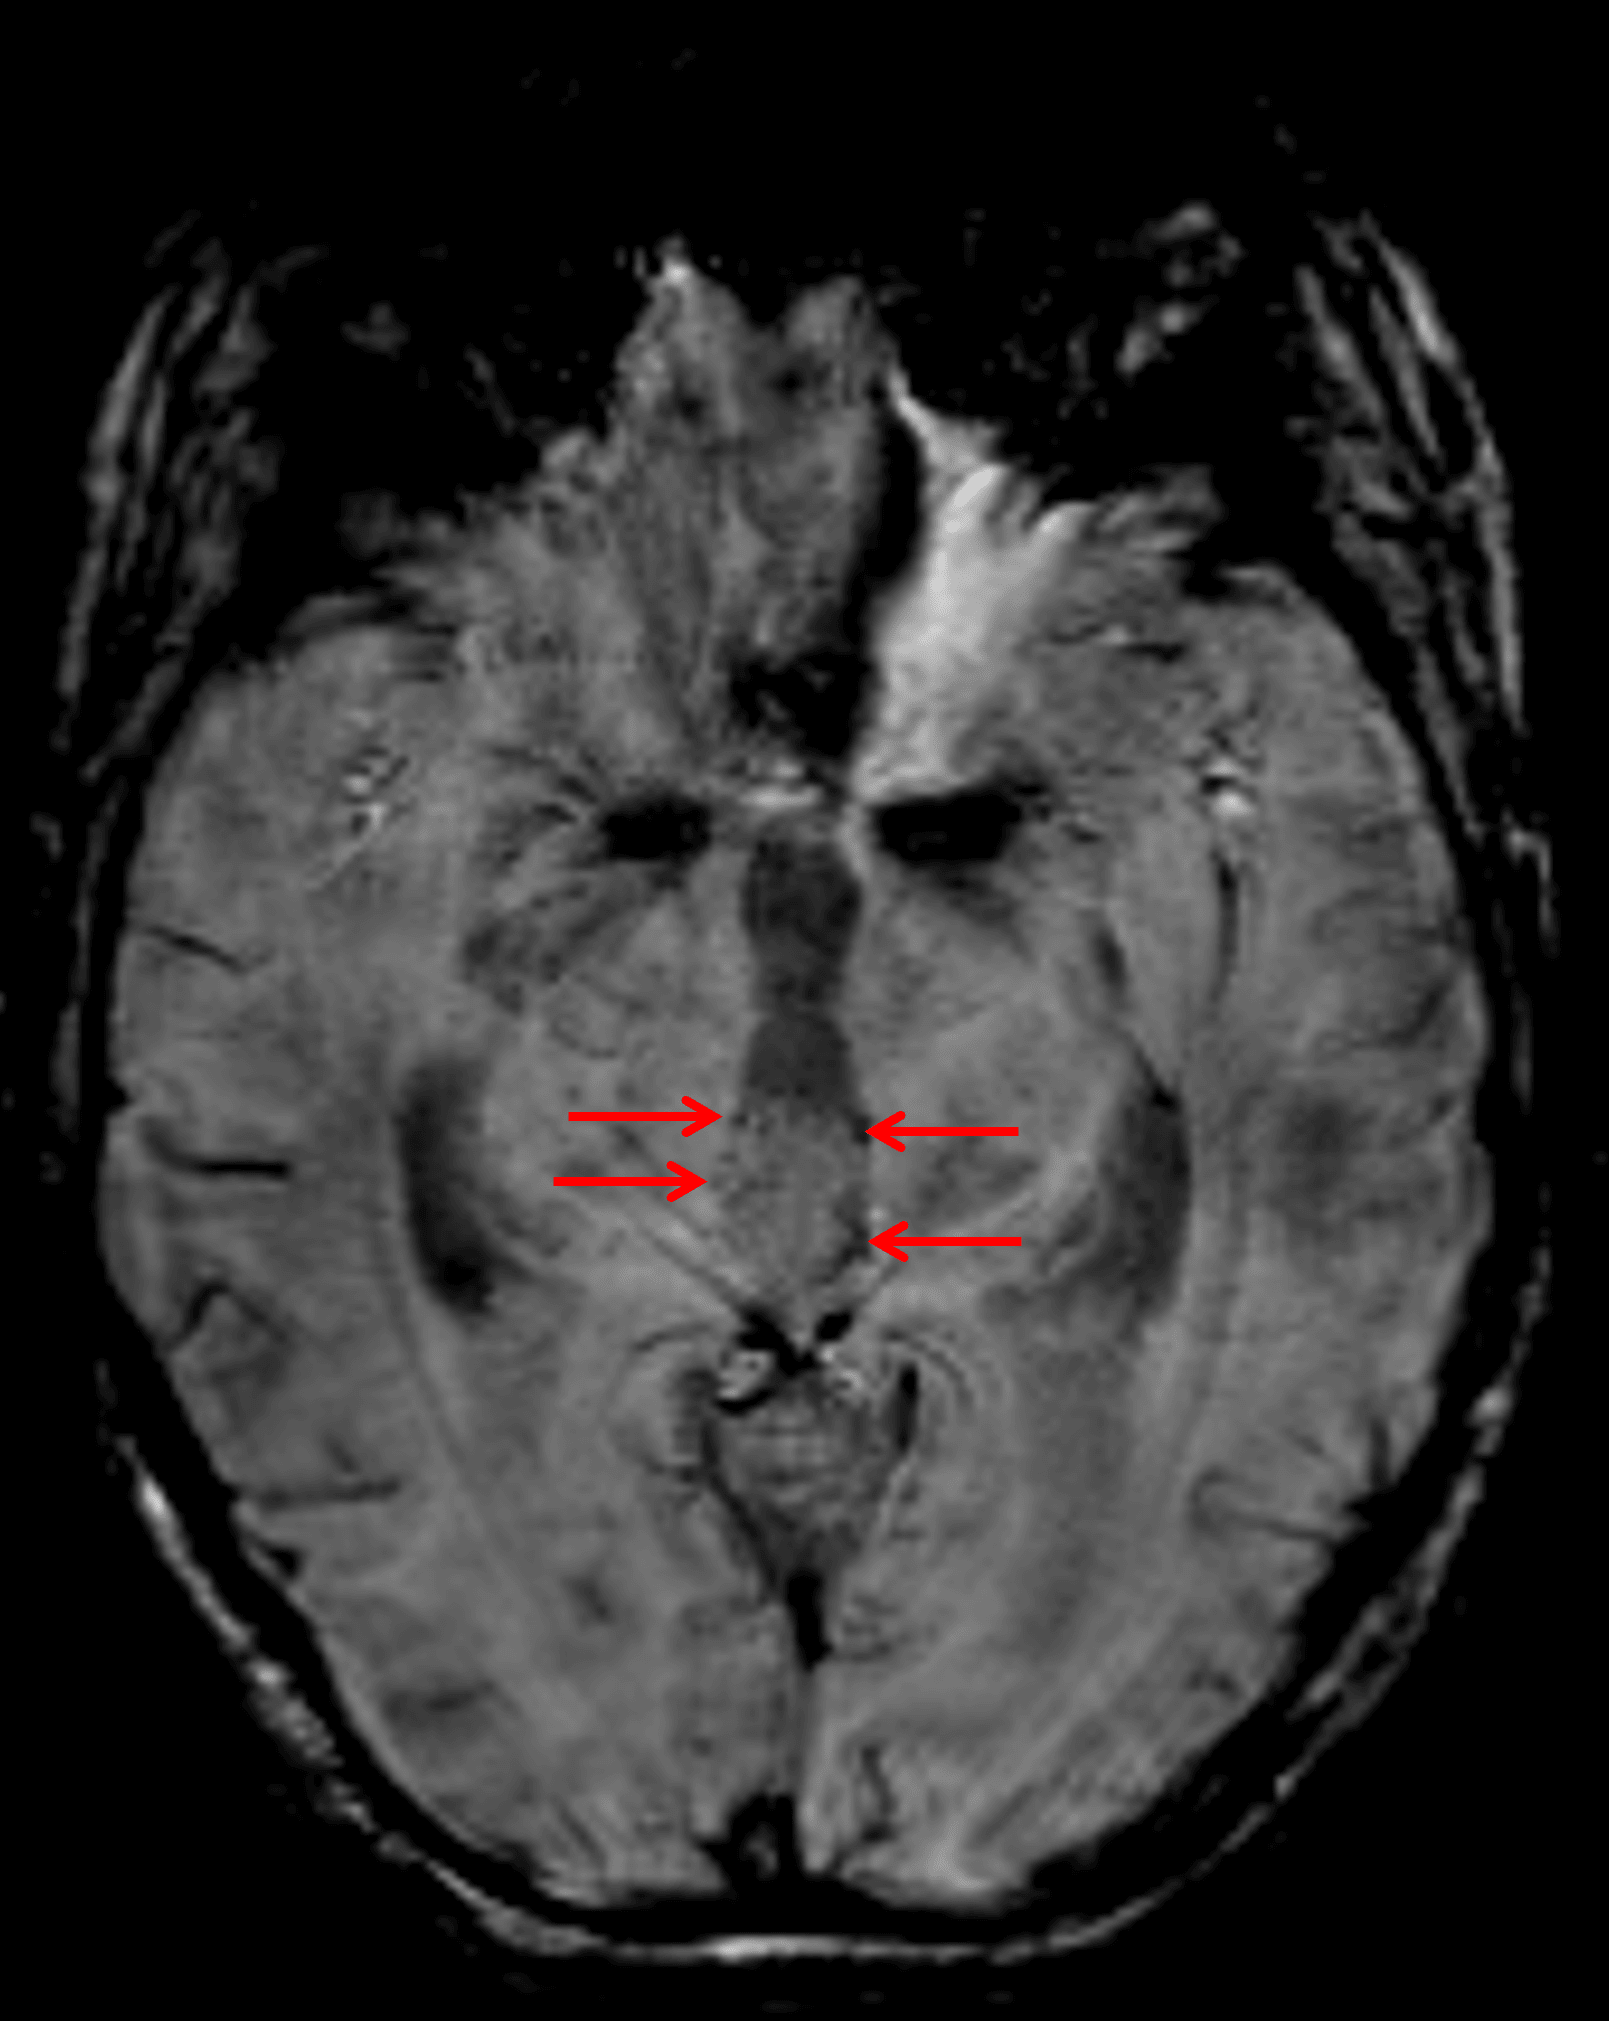

Foci of susceptibility artifact along the periphery of the mass (red arrows) represent peripheral calcification.